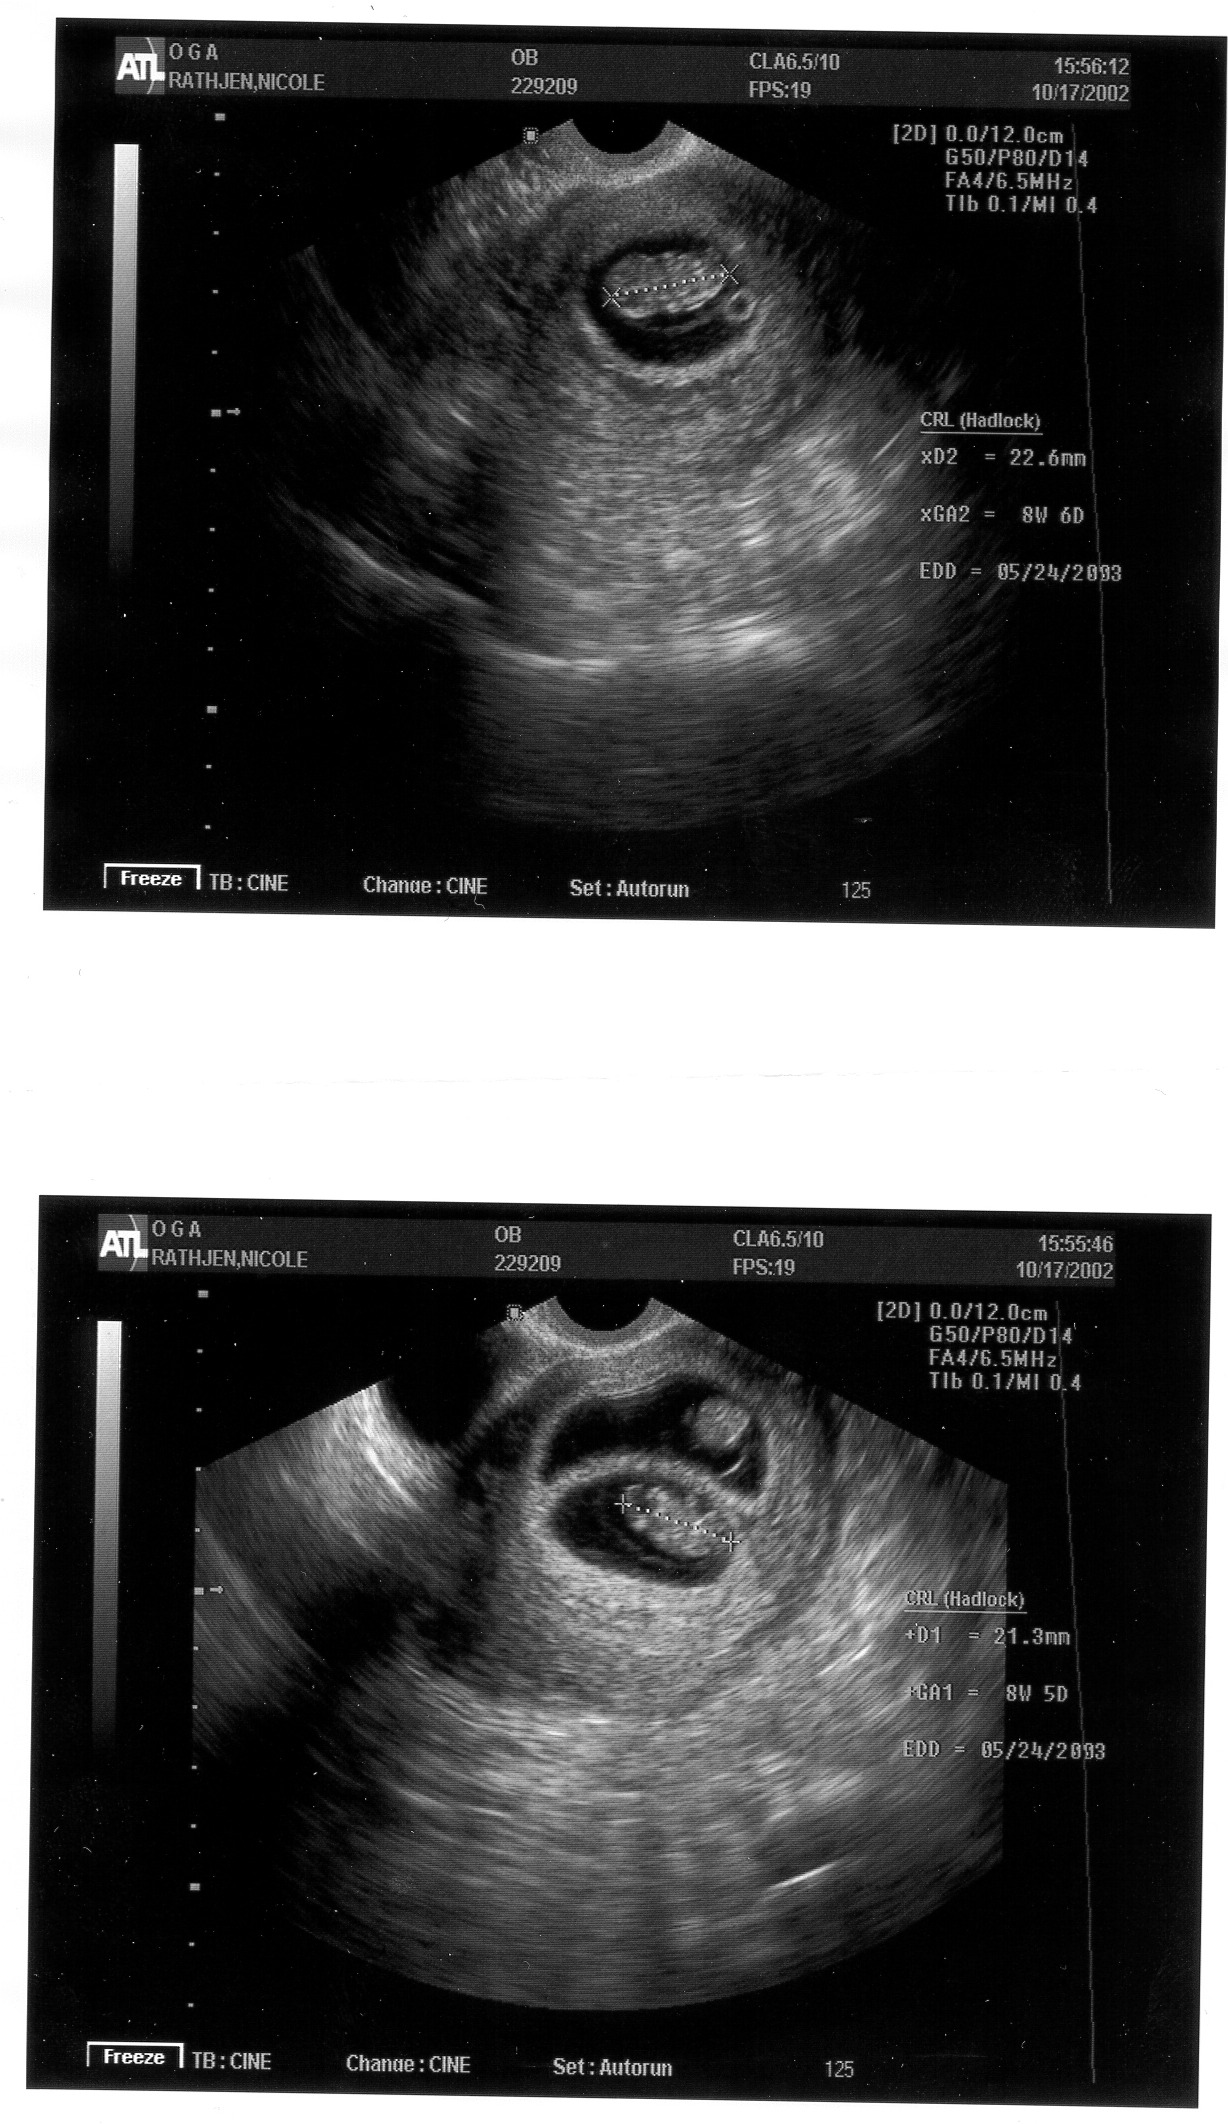

Our first baby pictures!!